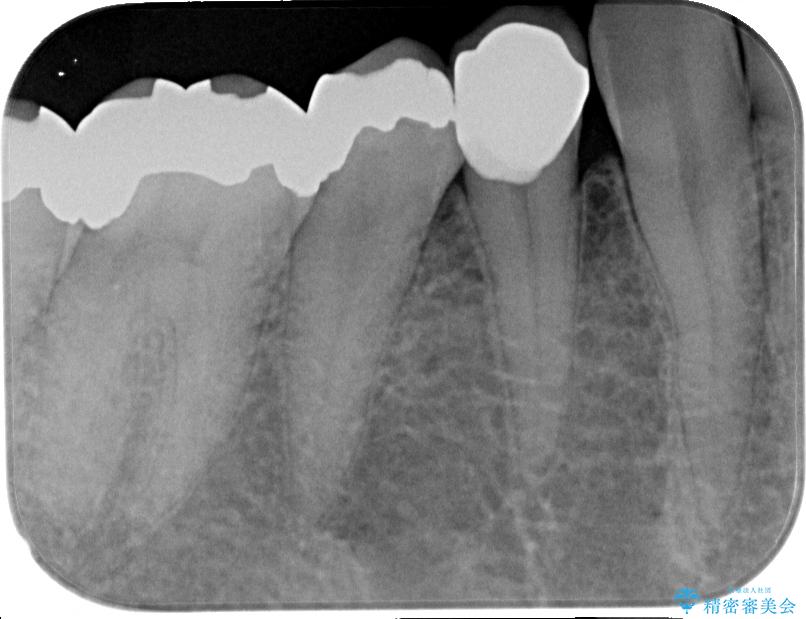

- 右下の銀歯が取れたとのことで来院された患者様です。以前にも取れていたところで、メタルインレーの不適合も認めていたため、次回外れたらオールセラミッククラウンにやり替えていくことを説明していたため、オールセラミッククラウンによる補綴治療を行っていくことにしました。

拡大鏡視野下で虫歯を除去しオールセラミッククラウンに適した形に整えました。